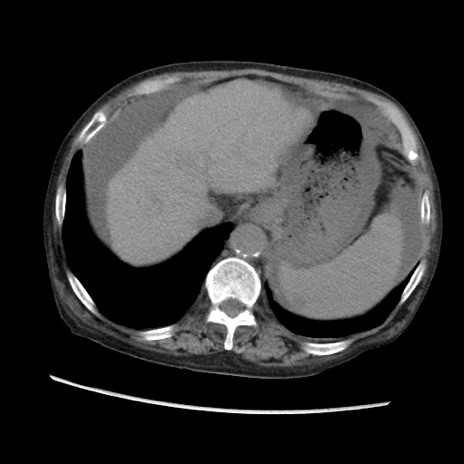

症例31(横断像)

【症例】80歳代 女性

【主訴】腹部膨満感

【現病歴】他院にて肝硬変にてフォロー中。1週間前から便秘、腹部膨満感、臍部腫瘤あり受診となる。

【既往歴】肝硬変

【身体所見】腹部膨隆あり、皮膚変化なし、疼痛なし。

【データ】WBC 4600、CRP 0.25